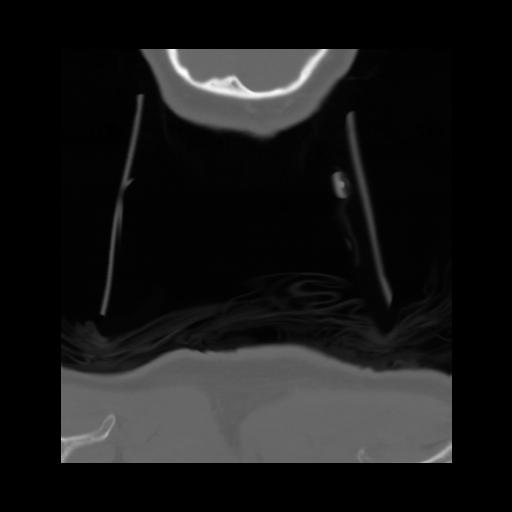

13 P.BLANDAS,,Coronal,2.000,P.BLANDAS,Coronal,